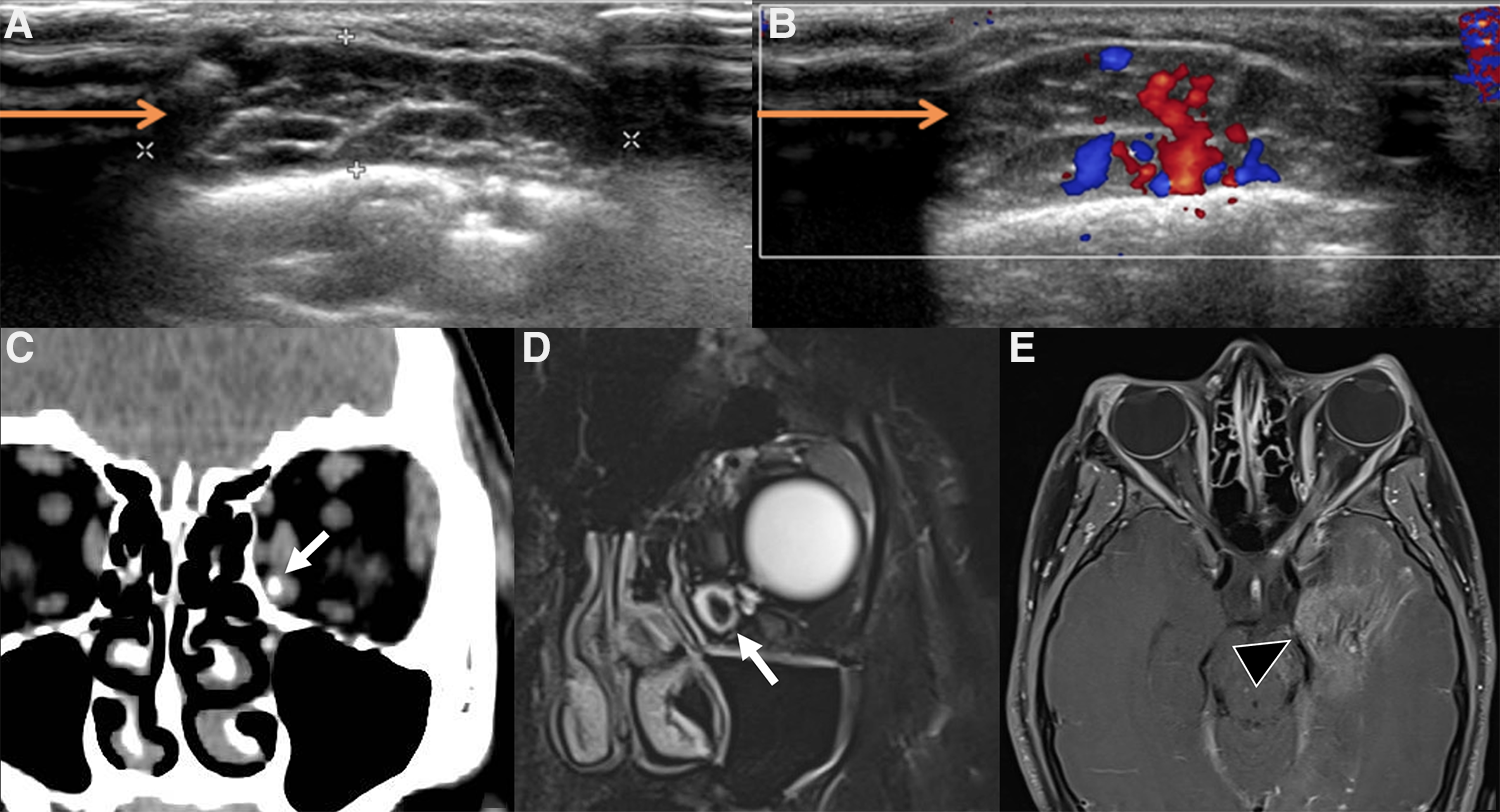

On US, venous malformations often present as compressible, well-marginated masses with a spongiform appearance from the presence of hypoechoic ectatic venous spaces separated by hyperechoic septa; they are generally heterogeneous and mostly hypoechoic when compared with the adjacent subcutaneous soft tissues, although occasionally they appear isoechoic or hyperechoic (58) (Figure 9). On color Doppler US, VMs are slow flow lesions, with very low vascular density. Spectral analysis in the veins reveals low-velocity flow with non-modulated spectrum; sometimes flow is so slow that can hardly be detected. In these cases, compression of the lesion may help, as compression on vascular channels can augment outflow and release can increase inflow (Figure 9). On MRI, they demonstrate increased signal intensity on T2w images, which is even better visualized on fat-suppressed sequences like STIR (Figure 9). As they are not high flow lesions, they do not show flow-voids on T2w sequences (59). Valsalva maneuver can also be performed during MRI examination (Valsalva-augmented MRI). Due to their hemodynamic milieu and histological features, VMs can undergo thrombosis or hemorrhage, thus exhibiting a more variable signal intensity both on T1 and T2w images. Phleboliths are seen as high density and very-low-signal intensity foci at CT (Figure 9) and MR, respectively (Figure 9): they are visible in roughly half the cases (8), but when they are present they are virtually pathognomonic. On post-contrast images, VMs show gradual filling. They lack arterial and early venous enhancement and enlarged feeding vessels or arterio-venous shunting, thus differentiating them from high-flow lesions. Less often, they may demonstrate nodular enhancement of tortuous vessels on delayed venous phase image (8). On CT, VMs appear as lobulated or multilobulated lesions, isodense to muscle, that can cross fascial planes. Not only is CT useful in identifying phleboliths, but also in revealing bone remodeling. Dynamic CT acquisition during contrast administration, with Valsalva maneuver performed during the venous phase, can make the dilation readily apparent in the case of distensible lesions, especially when small. Diagnostic angiography is rarely necessary unless strong venous pulsation or monophasic continuous subtle bruits are present, suggesting a large vascular connection with the venous system. Phlebography by direct puncture can be performed prior to injecting any sclerosing agent to delineate the size of the multiple compartments of the malformation and the degree of communication with the venous system (56).

Figure 9. Imaging of venous malformations. (A,B) US of a venous malformation of the lid in a 7-year-old boy. B-mode US (A) shows a compressible, relatively well-marginated mass with a “spongiform appearance” consisting of multiple anechoic dilated venous spaces separated by hyperechoic septa; on color Doppler US during Valsalva maneuver (B) a slight increase in size and increased representation of color-Doppler signal (baseline not shown) can be appreciated. (C–E) Coronal CT (C), coronal fat-suppressed T2-weighted image (D) and axial post-contrast fat-suppressed T1-weighted images (E) of a venous malformation of the orbit in a 13-year-old girl. A phlebolith within dilated venous channels is clearly evident at CT and MRI (target sign, white arrows in C,D); axial post-contrast FS T1 weighted image also shows an associated diffuse hemispheric venous drainage anomaly (black arrowhead in E).

The differential diagnosis of the masses of the orbit includes also lesions of neuronal origin. The “target sign” (Figure 14) is reported as typical of plexiform neurofibroma, but it is not specific and can also be seen in VMs (Figure 14). In the case of a plexiform neurofibroma, the typical appearance of the “target sign” (80) is that of a central component displaying low signal intensity on T2w images and subtle hyperechogenicity on US (corresponding at histopathology to central fibro-collagenous tissue) surrounded by a peripheral rim of high signal intensity on T2 weighted images and hypoechogenicity on US due to predominant myxoid tissue (81), while in venous malformations the central hypointense (T2w MRI) or hyperechoic (US) focus represents either a thrombus or a phlebolith in dilated venous channels (82) (Figure 14). Diffuse neurofibromas are less common, typically involve the skin and subcutaneous tissues, particularly of the head, and in MRI can mimic infantile and congenital hemangiomas (83).

Figure 14. Different forms of target sign on US. (A) Phlebolith within a venous malformation, appearing as a hyperechoic structure (black asterisk) surrounded by an anechoic formation which represents the dilated venous channel (black arrowhead). (B) Plexiform neurofibromas appear as non-compressible, polylobate lesion made up of multiple confluent tubular masses (black arrow), consisting of a slightly hyperechoic core (asterisk) surrounded by a hypo/anechoic halo (black arrow).